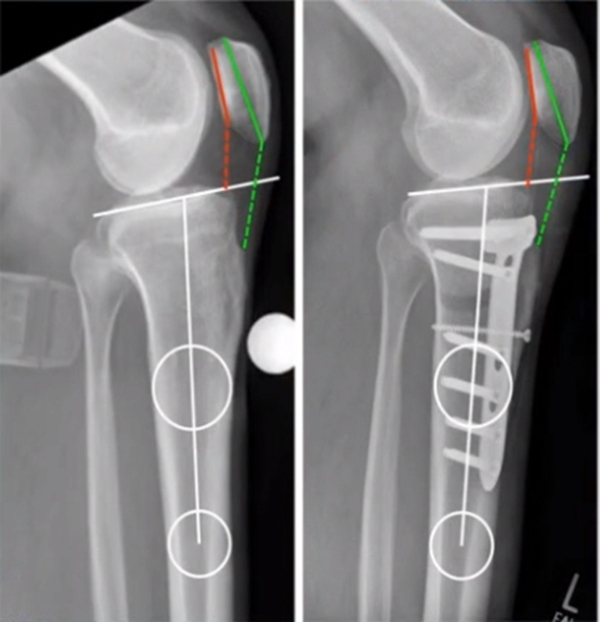

术中先打克氏针确定截骨方向,先做关节内截骨,截完后测量下肢力线,发现并没达到术前设计的Fujisawa点。

术中影像资料

随后用骨刀继续向前敲,做HTO内侧开放楔,截骨完成后内侧固定,并测量下肢力线,此时达到术前设计的要求。

最终力线

术后检查证实达到了术前预期的手术效果,关节线达到了平行,半脱位得到矫正,同时关节线和地面水平。病人行走达到了理想的效果。

术后X线